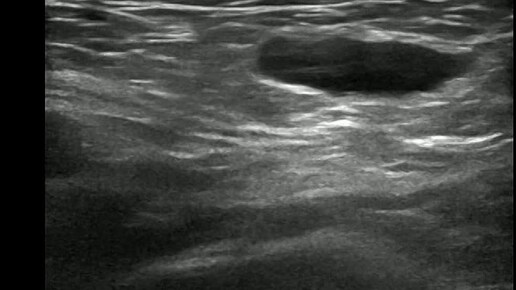

Видео к статье: Гидроцеле канала Нукка. https://dzen.ru/a/aDAxMOvxqQcgJkGG

Ультразвуковые находки от врача УЗД Зорина Я.П.